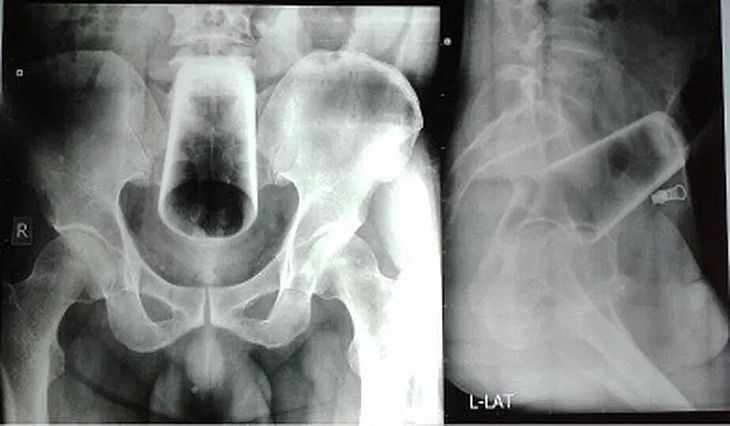

As radiografias mostraram um copo em posição invertida na parte superior do reto e cólon. A primeira tentativa para remover o vidro do reto do paciente foi manual. Mas a estratégia não obteve sucesso porque o vidro “não podia ser agarrado para remoção” e havia “risco significativamente alto de quebra do vidro que poderia, por sua vez, levar a lesões no intestino”, escreveram os médicos.